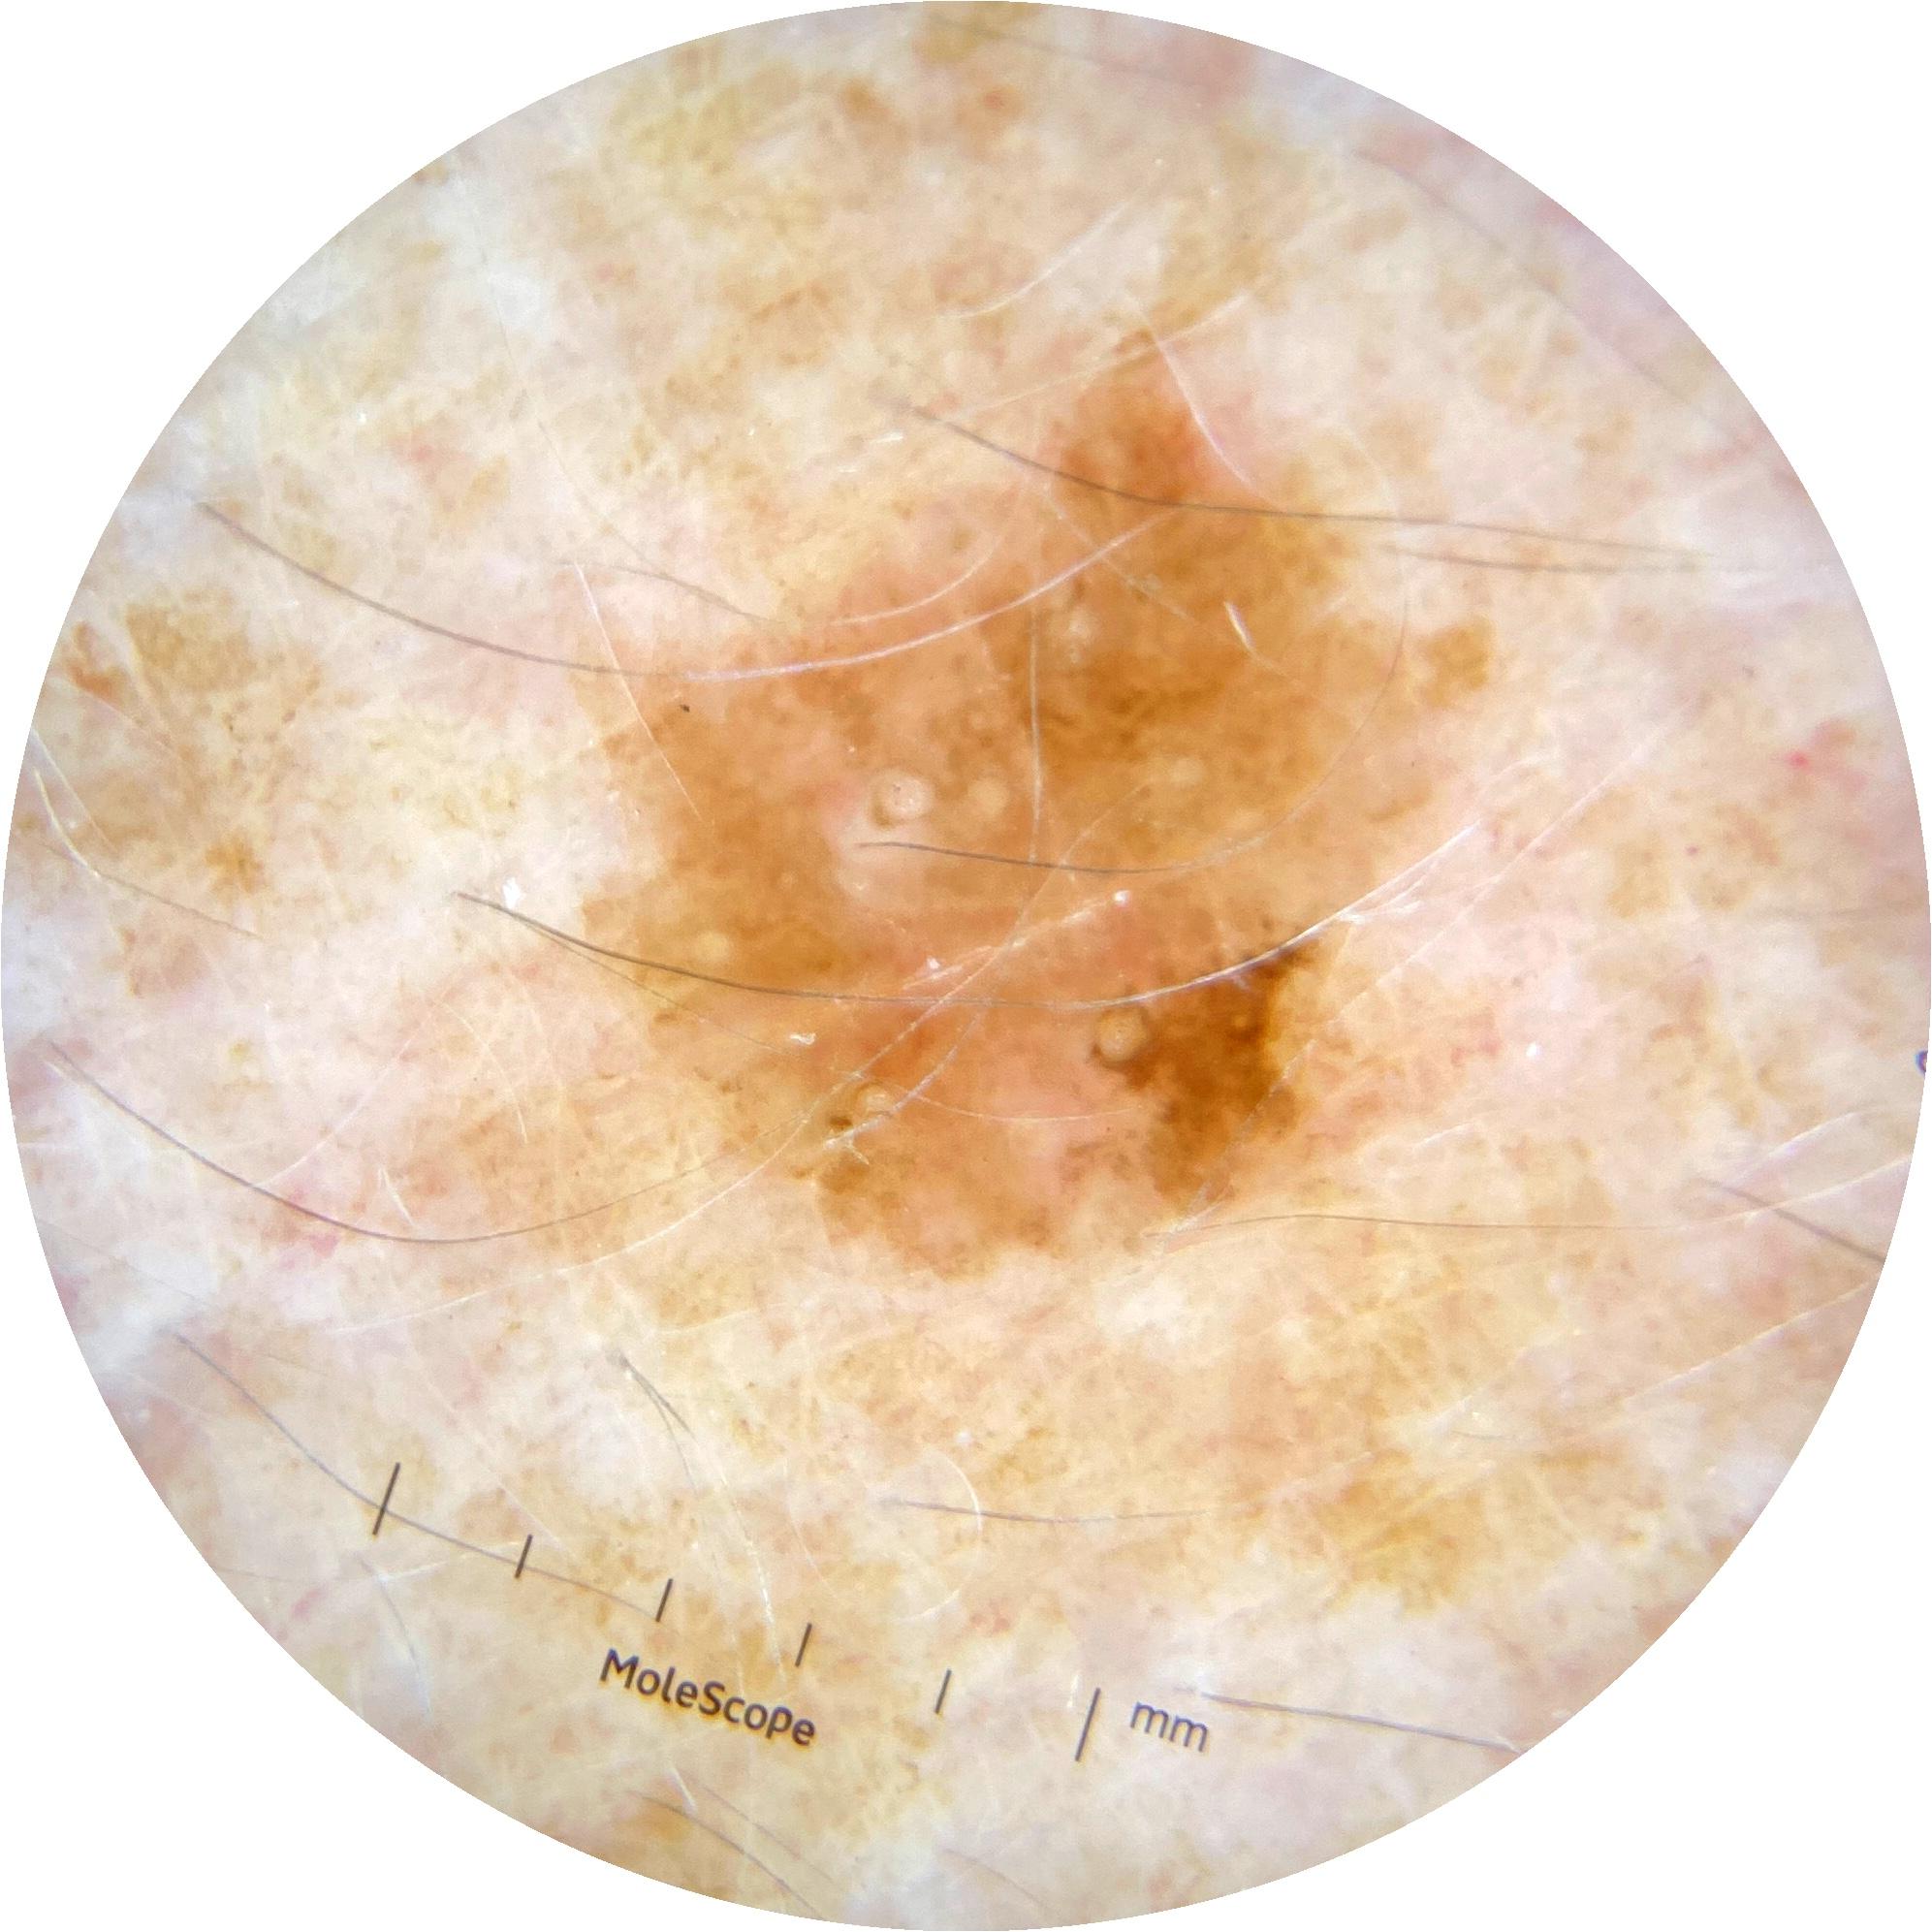

ISIC_8490164

2003 x 2003

MEL-SELF Trial, https://www.sydney.edu.au/medicine-health/our-research/research-centres/melself-project.html

acquisition_day 218

age_approx 65

anatom_site_1 Upper extremity

anatom_site_general upper extremity

diagnosis_1 Benign

diagnosis_confirm_type single image expert consensus

fitzpatrick_skin_type I

image_type dermoscopic